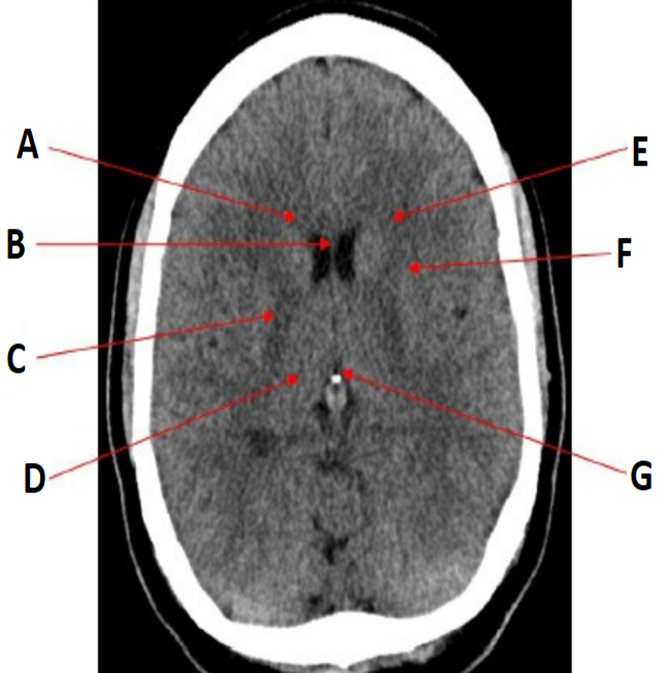

how do you interpret CT images

•CT images are displayed as varying shades of grey based on the attenuation that different tissues exhibit.

•The Hounsfield Unit (HU) is an arbitrary scale which is used to display the range of tissue densities when viewing a CT scan: the scale ranges from -1,000 to +1,000, with water by convention designated the value of 0.

The higher the HU, the brighter (or denser) the tissues displayed

label